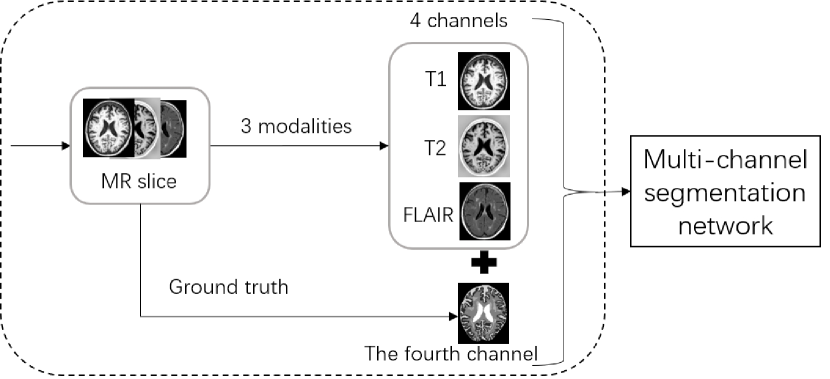

Basic Experiment. We conducted a basic experiment, in which we trained the multi-channel segmentation network with input of 4 channels including T1, T2-FLAIR, T1-IR and a fourth channel that is its own ground truth (Figure 1) and the average dice ratio is higher than 0.97. It could conclude that the fourth channel with the ground truth provides a priori texture information to the network, making the network performs very well. However, the test data don’t have ground truth, so we proposed a new method which does not require its ground truth and can achieve similar effects. We use CBIR to match each slice with the best similar image’s ground truth. Then the network can use the information provided to facilitate segmentation.

Refer to caption

Figure 1: Basic experiment. The input of the forth channel is its ground truth.